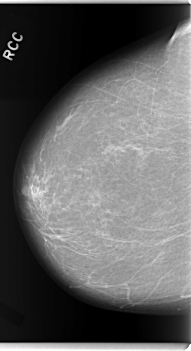

C_0114_1.RIGHT_CC

RIGHT_CC LINES 5952 PIXELS_PER_LINE 3232 BITS_PER_PIXEL 12 RESOLUTION 50 NON_OVERLAY